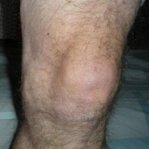

Obrzęk i stan zapalny stawu kolanowego są sygnałem ostrzegawczym poważnych zaburzeń. Bez leczenia może to prowadzić do całkowitej utraty sprawności ruchowej i konieczności interwencji chirurgicznej. Reaguj natychmiast na pierwsze objawy!